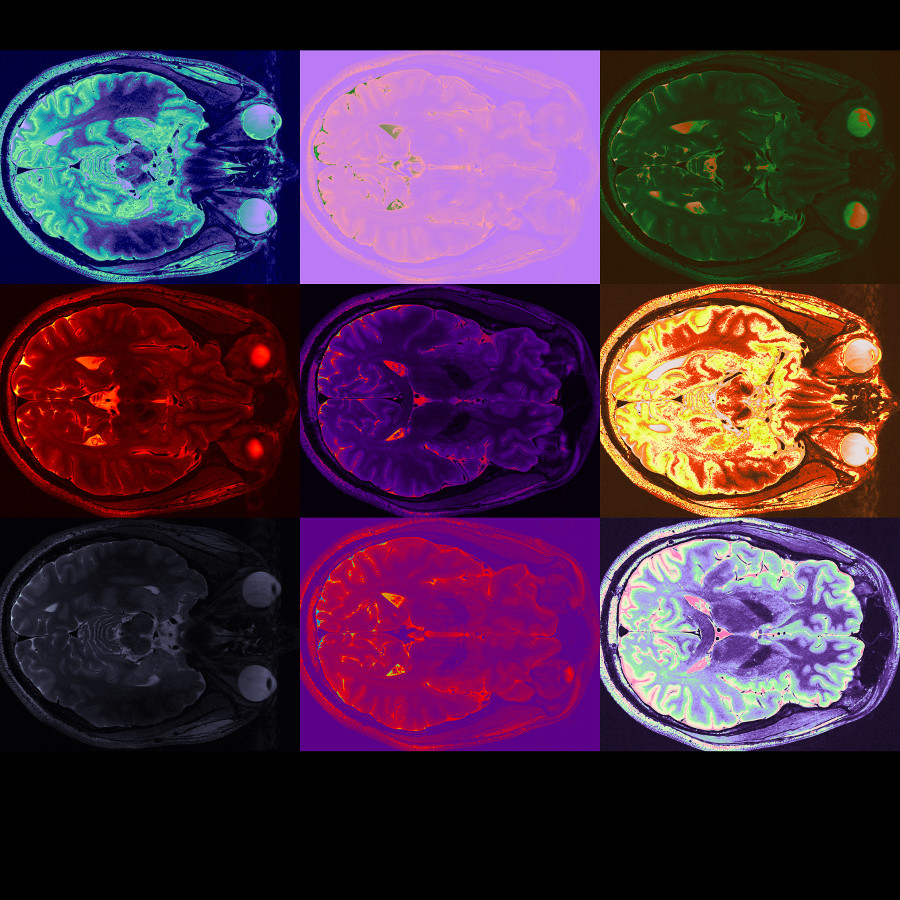

(8) Warhol_small